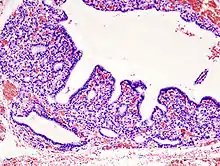

![]() Hyperplasia of the thyorid follicles in hyperthyroidism, H&E staining. |